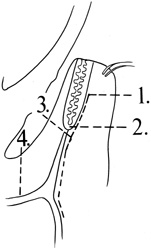

surface of the lateral rim.  Fig. 7. Coronal schematic view demonstrating major vessels penetrating periorbita

and traversing the extraperiosteal space that may be encountered during

periorbital elevation. (A, zygomaticotemporal artery; B, zygomaticofacial artery; C, communicating branch of infraorbital artery: D, supraorbital artery: E, posterior ethmoidal artery: F, anterior ethmoidal artery.) Fig. 7. Coronal schematic view demonstrating major vessels penetrating periorbita

and traversing the extraperiosteal space that may be encountered during